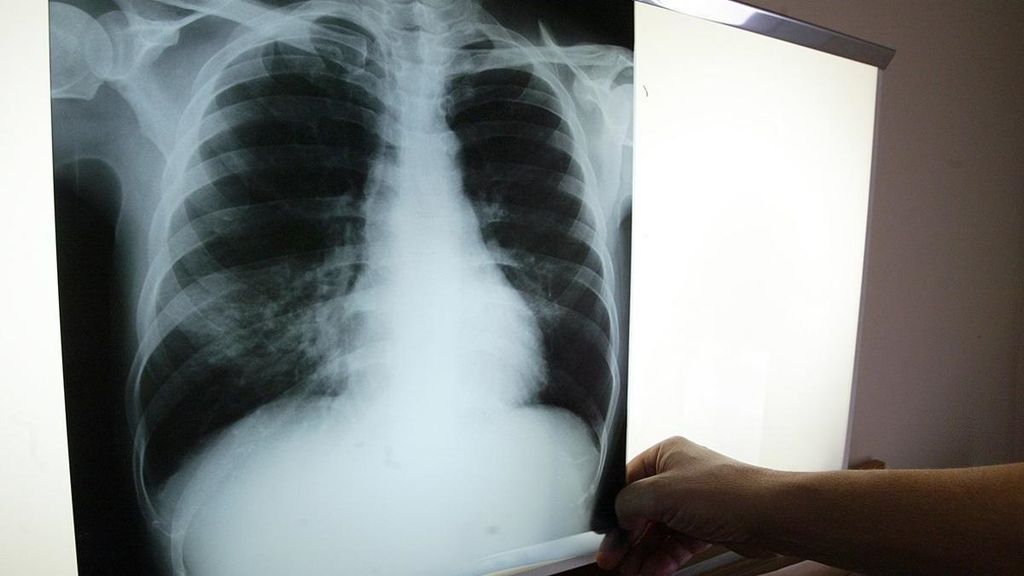

Para contextualizar, la tuberculosis es una enfermedad infecciosa causada por la bacteria Mycobacterium tuberculosis o bacilo de Koch, que afecta principalmente los pulmones, aunque puede comprometer otros órganos del cuerpo. Se transmite por el aire a través de las gotas microscópicas que expulsa una persona infectada al toser, lo que permite que otras personas sanas inhalen la bacteria.

El Día Mundial de la Tuberculosis, celebrado el 24 de marzo, destacó la importancia de la prevención y detección temprana. Christián Lombardi, referente del programa de tuberculosis de la Seremi de Salud, explicó que el síntoma más común de la enfermedad es la tos con flema que dura más de dos semanas, junto con fiebre, sudoración nocturna y pérdida de peso. "El diagnóstico es gratuito en el sistema público de salud para todos los ciudadanos, sin importar su previsión de salud", indicó Lombardi.